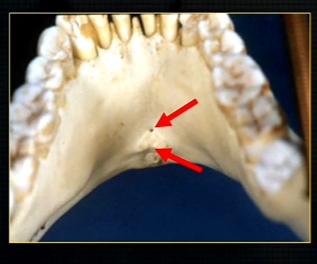

anterior lingual/inner aspect of the mandible

bony spurs

genial tubercules - muscles of the tongue and neck attach here

lingual pit

lower occlusal

small bony spurs of the genial tubercles